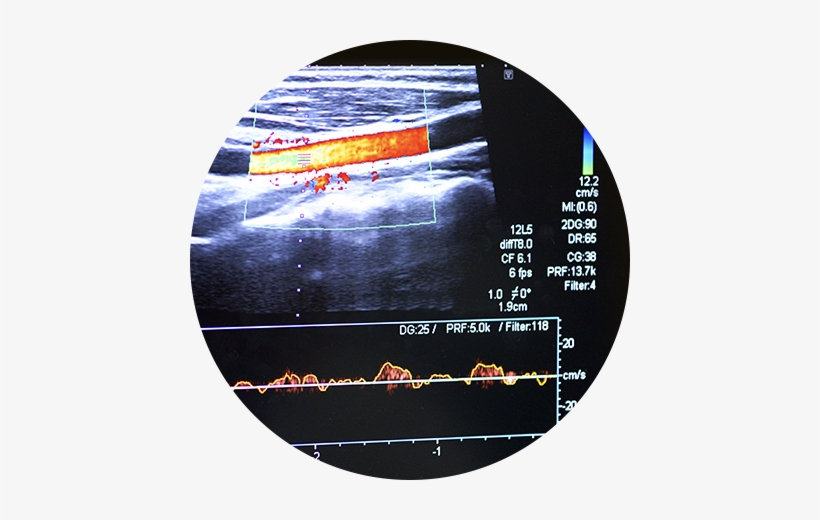

From dxodpcmko.blob.core.windows.net

What Does Blood Clot In Arm Look Like On Ultrasound at Dale Fischer blog Blood Clot In Arm a blood clot in the arm can be dangerous if it travels to the lungs. thrombosis is a serious condition where blood clots form in your blood vessels or heart. asvt is a type of blood clot in your upper arm that can cause pain, swelling and discoloration. learn how to recognize the signs of a. Blood Clot In Arm.